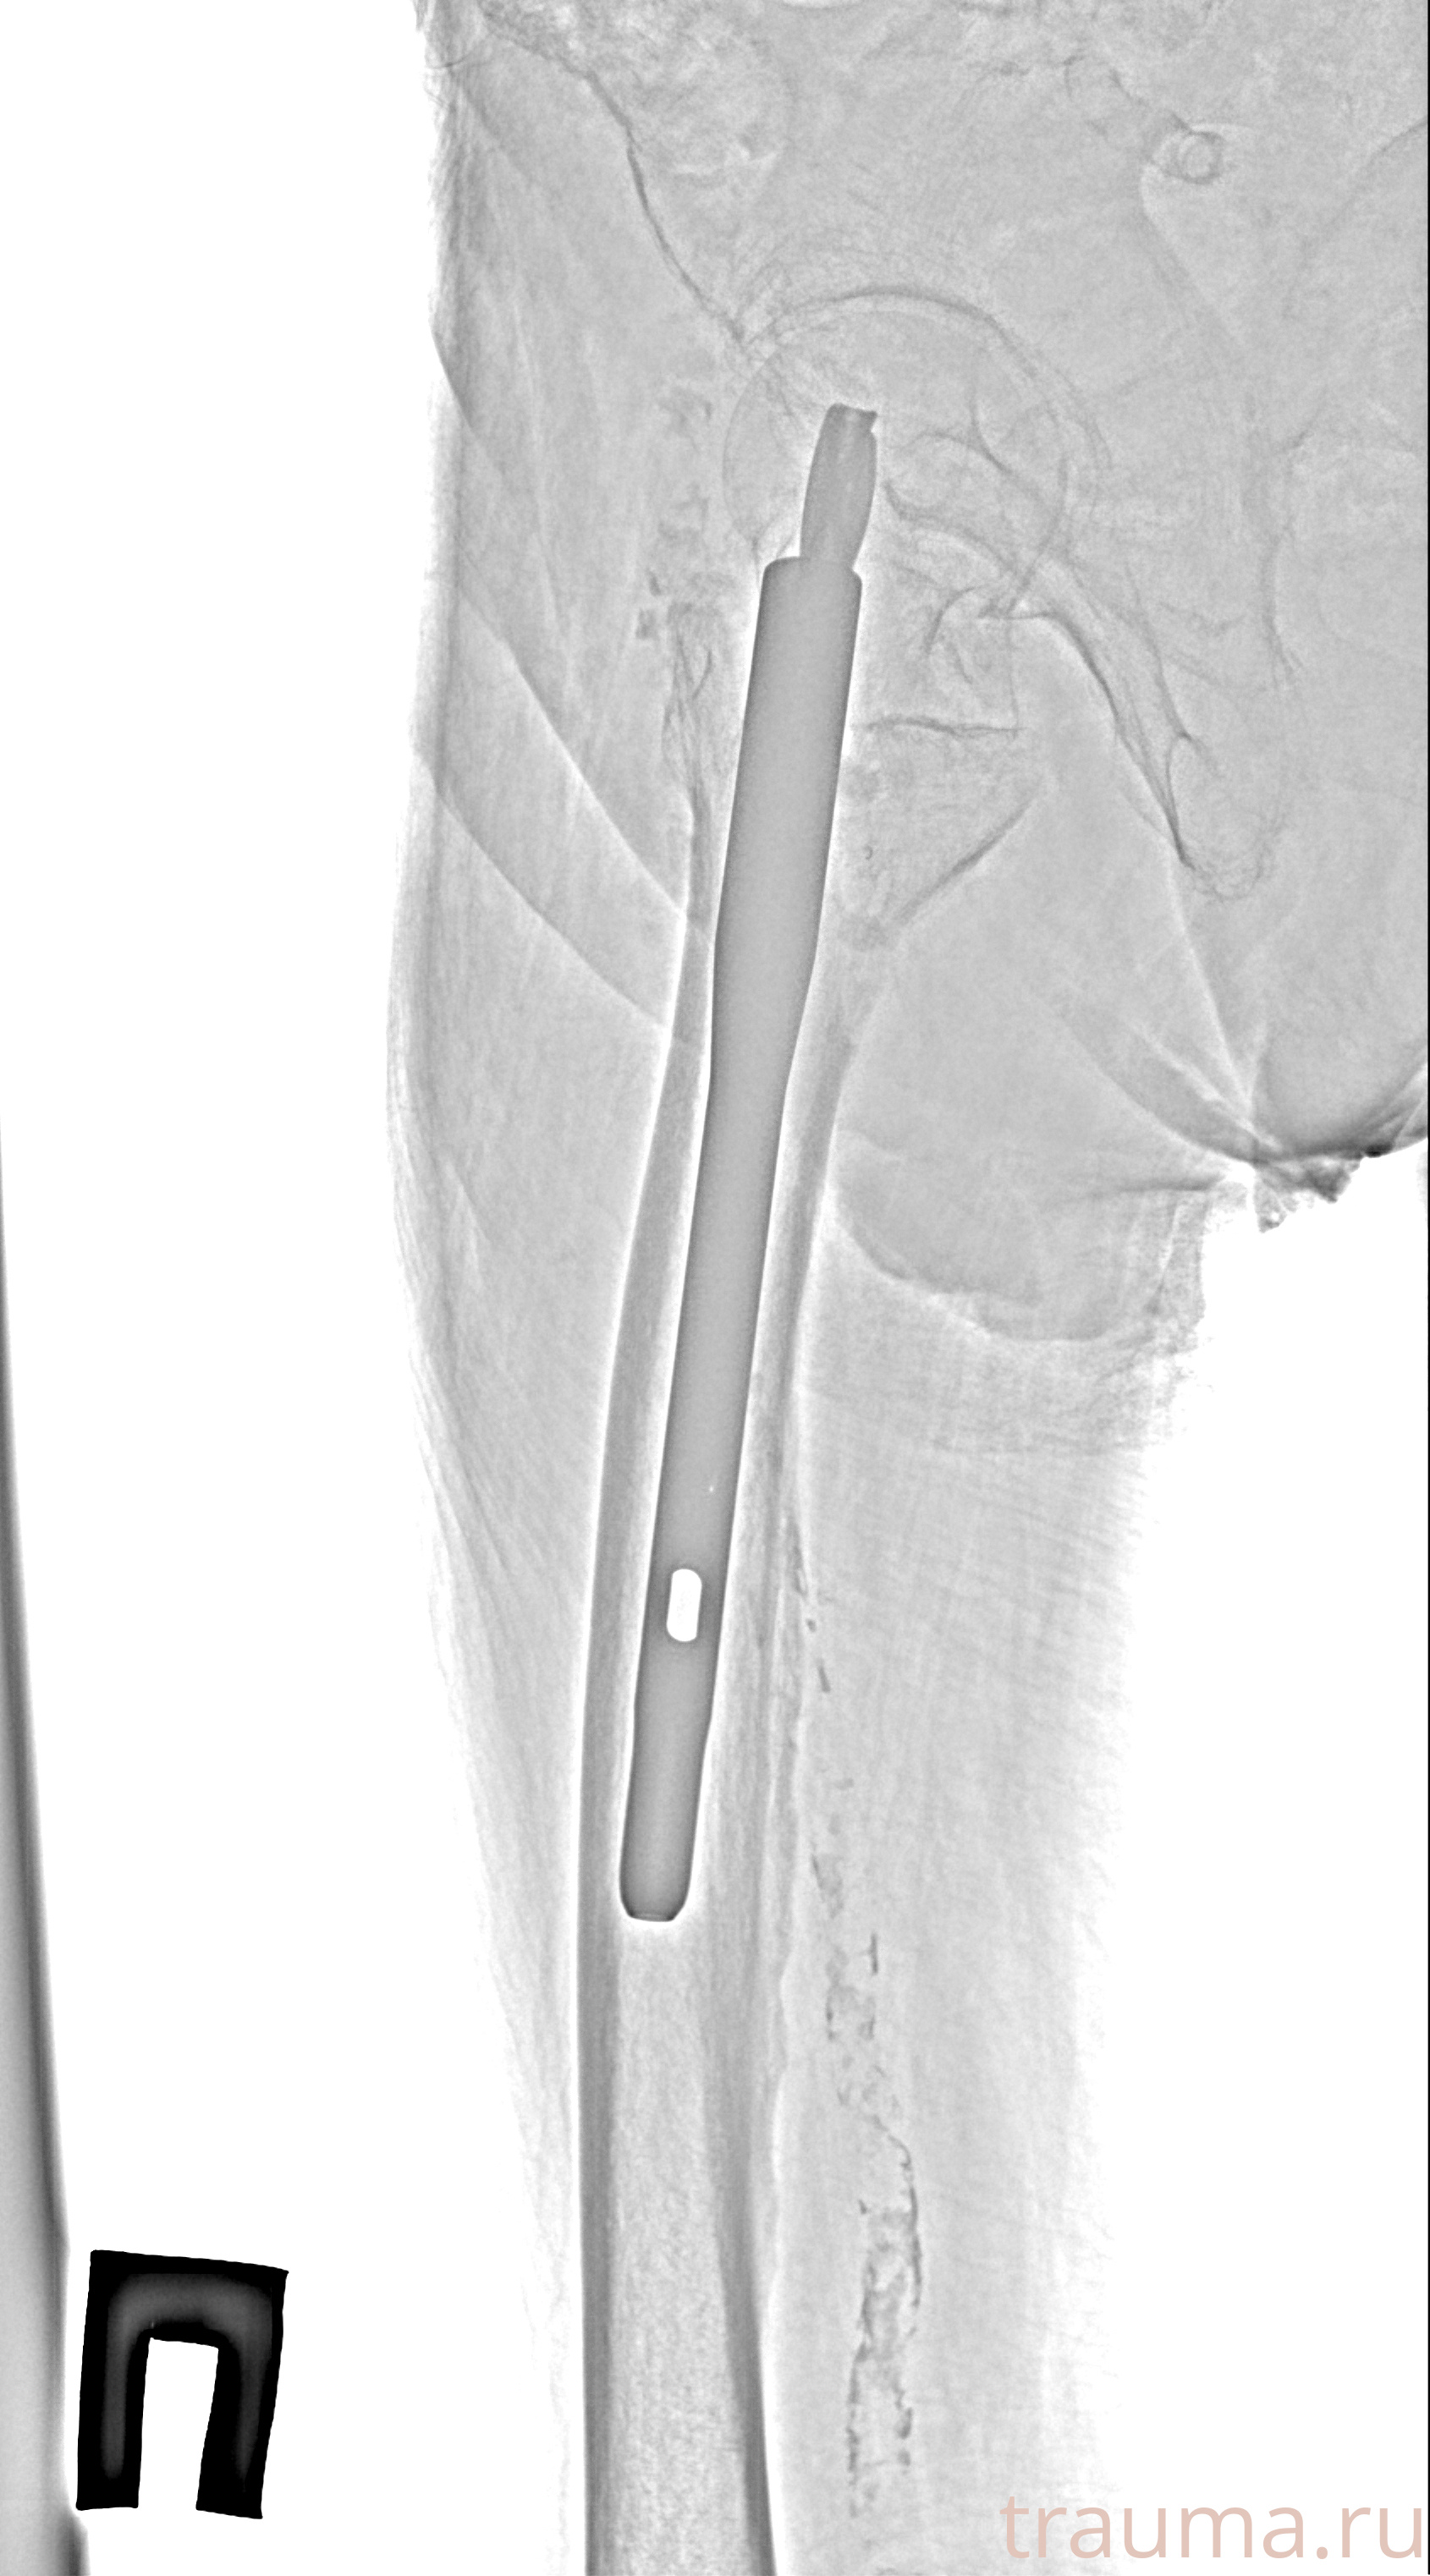

Рентгенограммы